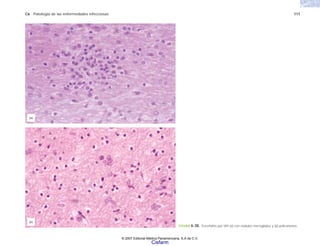

FIGURA 6-30. Encefalitis por VIH (a) con nódulos microgliales y (b) policariones.

(b)

(a)

© 2007 Editorial Médica Panamericana, S.A de C.V.